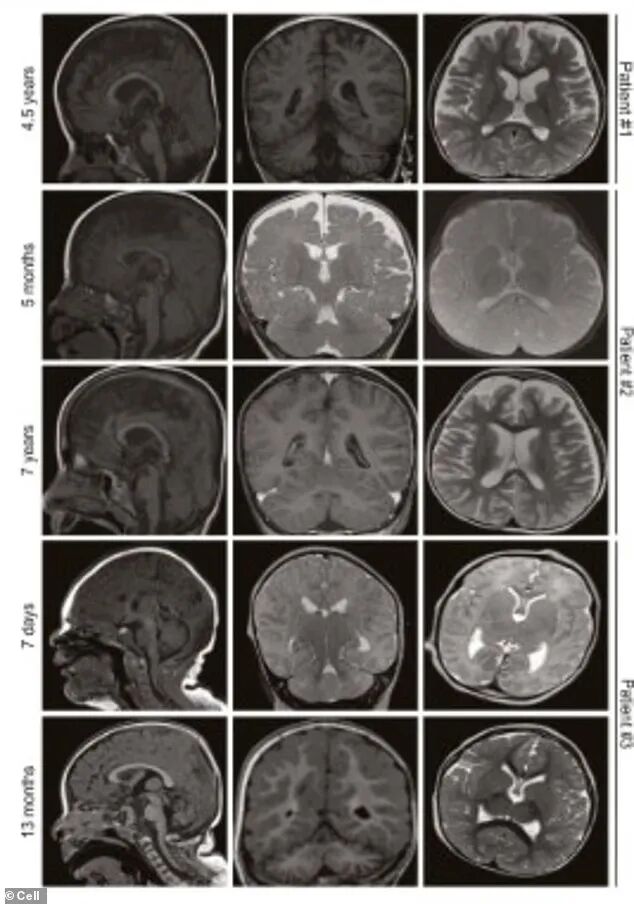

脑部扫描显示“萎缩”。患者的核磁共振扫描显示,小脑、协调中心逐渐收缩,两名患者的大脑皮层收缩,涉及记忆和思维。(图自:《细胞》杂志)